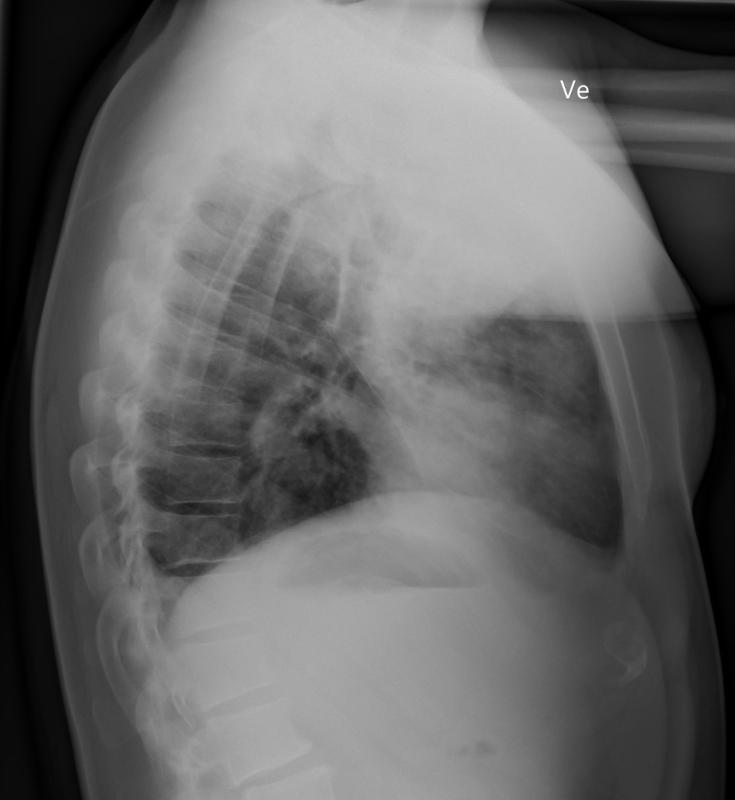

第 2 天复查胸部 X 光检查显示左肺和右上叶有明显进展的实变浸润,进一步支持弥漫性肺泡损伤和微出血的诊断,并怀疑存在 ARDS。